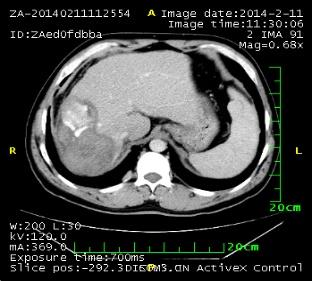

2010年10月,腹部CT提示肝脏占位,考虑肝癌。

2014年2月11日复查,发现双肺多发转移瘤增多增大,明确为疾病进展。

1. 肝脏原发病灶治疗前后磁共振扫描结果对比

淫羊藿素软胶囊治疗3、6、16、18个月后,肝脏病变呈现消融后改变,未观察到病灶进展。